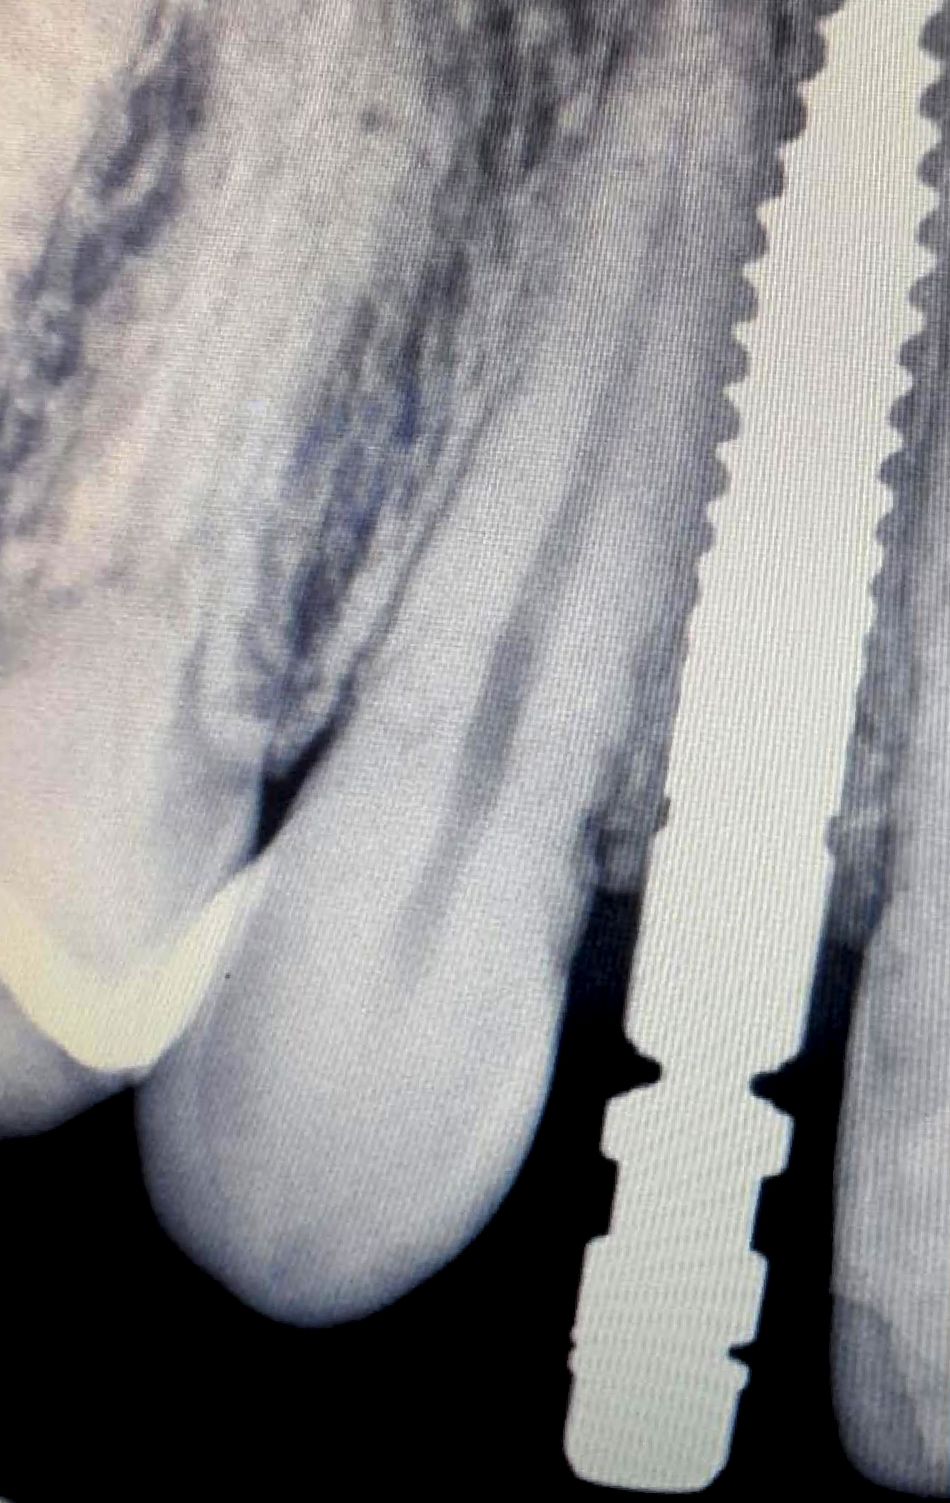

After an assessment of periapical radiography (Fig. 6), cone beam computed tomography (Fig. 7-8) and a clinical evaluation of tooth 12, it was decided that a Straumann® BLT Ø 2.9 mm was a good solution for this clinical case due to the narrow interdental space and limited horizontal bone available (5.25 mm).

The final images show the clinical situation at 16 months of follow-up after implant insertion. A periapical radiograph was taken using a Kodak RVG 5200 sensor (Carestream®) during this visit, in which it is possible to see the stability of the tissues. (Fig. 33-34)